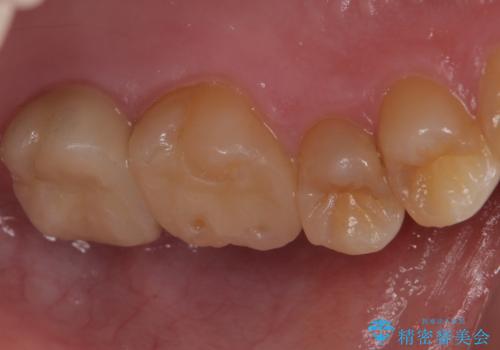

- 奥歯に穴が開いた気がするとのことで来院。

検査の結果、左上の奥歯に大きな虫歯があることが確認できました。

患者様のご希望もあり、今回はセラミックでの治療となりました。

歯の表面に穴が開くほどの虫歯は歯の中でかなり大きくなっていることが多いです。

虫歯の除去後は適合の良い修復物を入れることで今後の虫歯リスクを減らします。